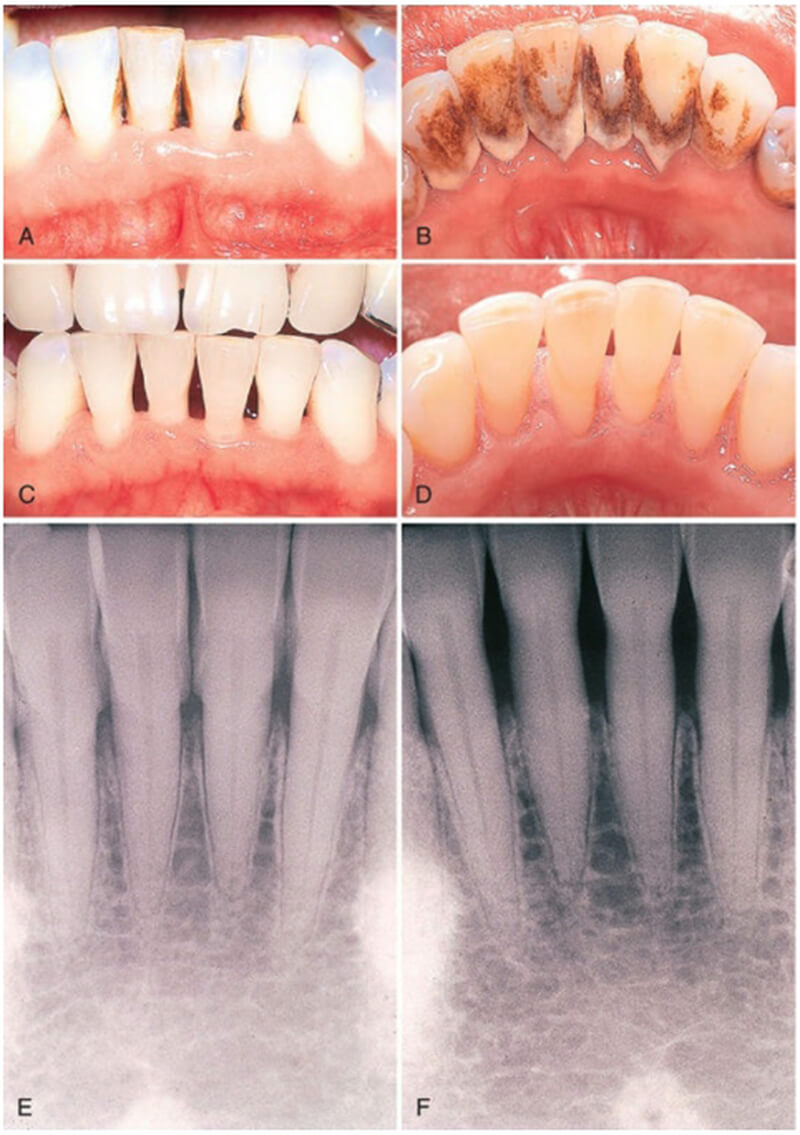

(3)牙面著色,經常吸煙,核查的人牙面上會有煙斑,茶漬,不僅不美觀,引起牙周疾病,影響健康。只能徹底清除菌斑、牙結石、才能保持牙周健康!

洗牙會流血,牙縫還會越來越大?

洗牙會出血是因為牙結石上的細菌造成牙齦發炎、腫脹,當牙結石清除乾淨,發炎的牙齦逐漸消腫,流血的狀況便自然會改善。

當你牙齒有牙結石時,是牙結石把牙縫堵住了,洗牙時會將牙結石移除,原本的牙縫顯露出來,當舌頭在碰觸牙齒時已不會碰觸到牙結石,可直接觸碰到牙縫,所以會有洗完牙牙縫變大錯覺,這是正常的現象。

牙齒鬆動的狀況只有嚴重的牙周病患者才會出現,當牙結石長久累積,導致牙齦反覆發炎,長期下來會有牙齦萎縮、齒槽骨被吸收的狀況發生,這時牙結石仍填滿牙縫,會讓人有牙齒仍屹立不搖的錯覺。當洗牙後牙結石被移除,才發現牙齒早已失去支撐的根基,無齒槽骨、牙齦的保護,才會造成牙齒鬆動。